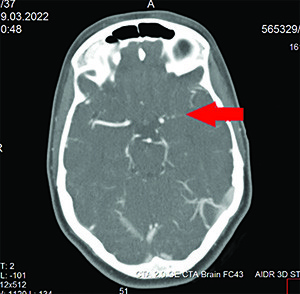

Пациентке выполнены КТ головного мозга и КТ-ангиография.

Рисунок 1. Результат проведения КТ-ангиографии: окклюзия левой ВСА до М1-сегмента.На КТ ГМ: патологических объемных образований головного мозга не выявлено. Денситометрические показатели вещества головного мозга соответствуют нормальным величинам. Желудочки мозга, кортикальные борозды, базальные цистерны обычных размеров. Срединные структуры не смещены. Турецкое седло обычной формы, размеров.

Ретробульбарные пространства свободны. Признаков костно-травматических и костно-деструктивных изменений свода и основания черепа не выявлено. Ячейки пирамид и сосцевидных отростков височных костей воздушны, без особенностей. Пневматизация придаточных пазух носа на уровне сканирования не нарушена.

При выполнении КТ-ангиографии головного мозга выявлена окклюзия левой ВСА до М1-сегмента (см. рис. 1).